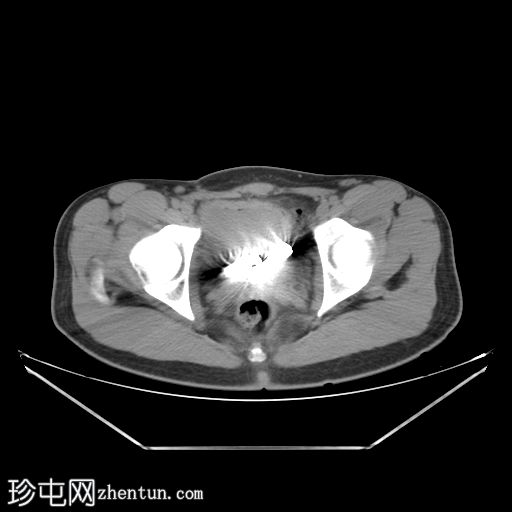

CT扫描

膀胱内可见两个圆柱形金属物体,导致金属伪影。

膀胱内可见两个圆柱形电池。经进一步询问,患者自述为寻求性刺激而将两个电池经尿道插入。

吞食(或如本例所示插入)电池可能导致多种并发症,例如器官穿孔、瘘管形成、狭窄或因瘘管通向大血管而导致的血管内渗漏。纽扣电池或硬币电池更容易引起并发症。